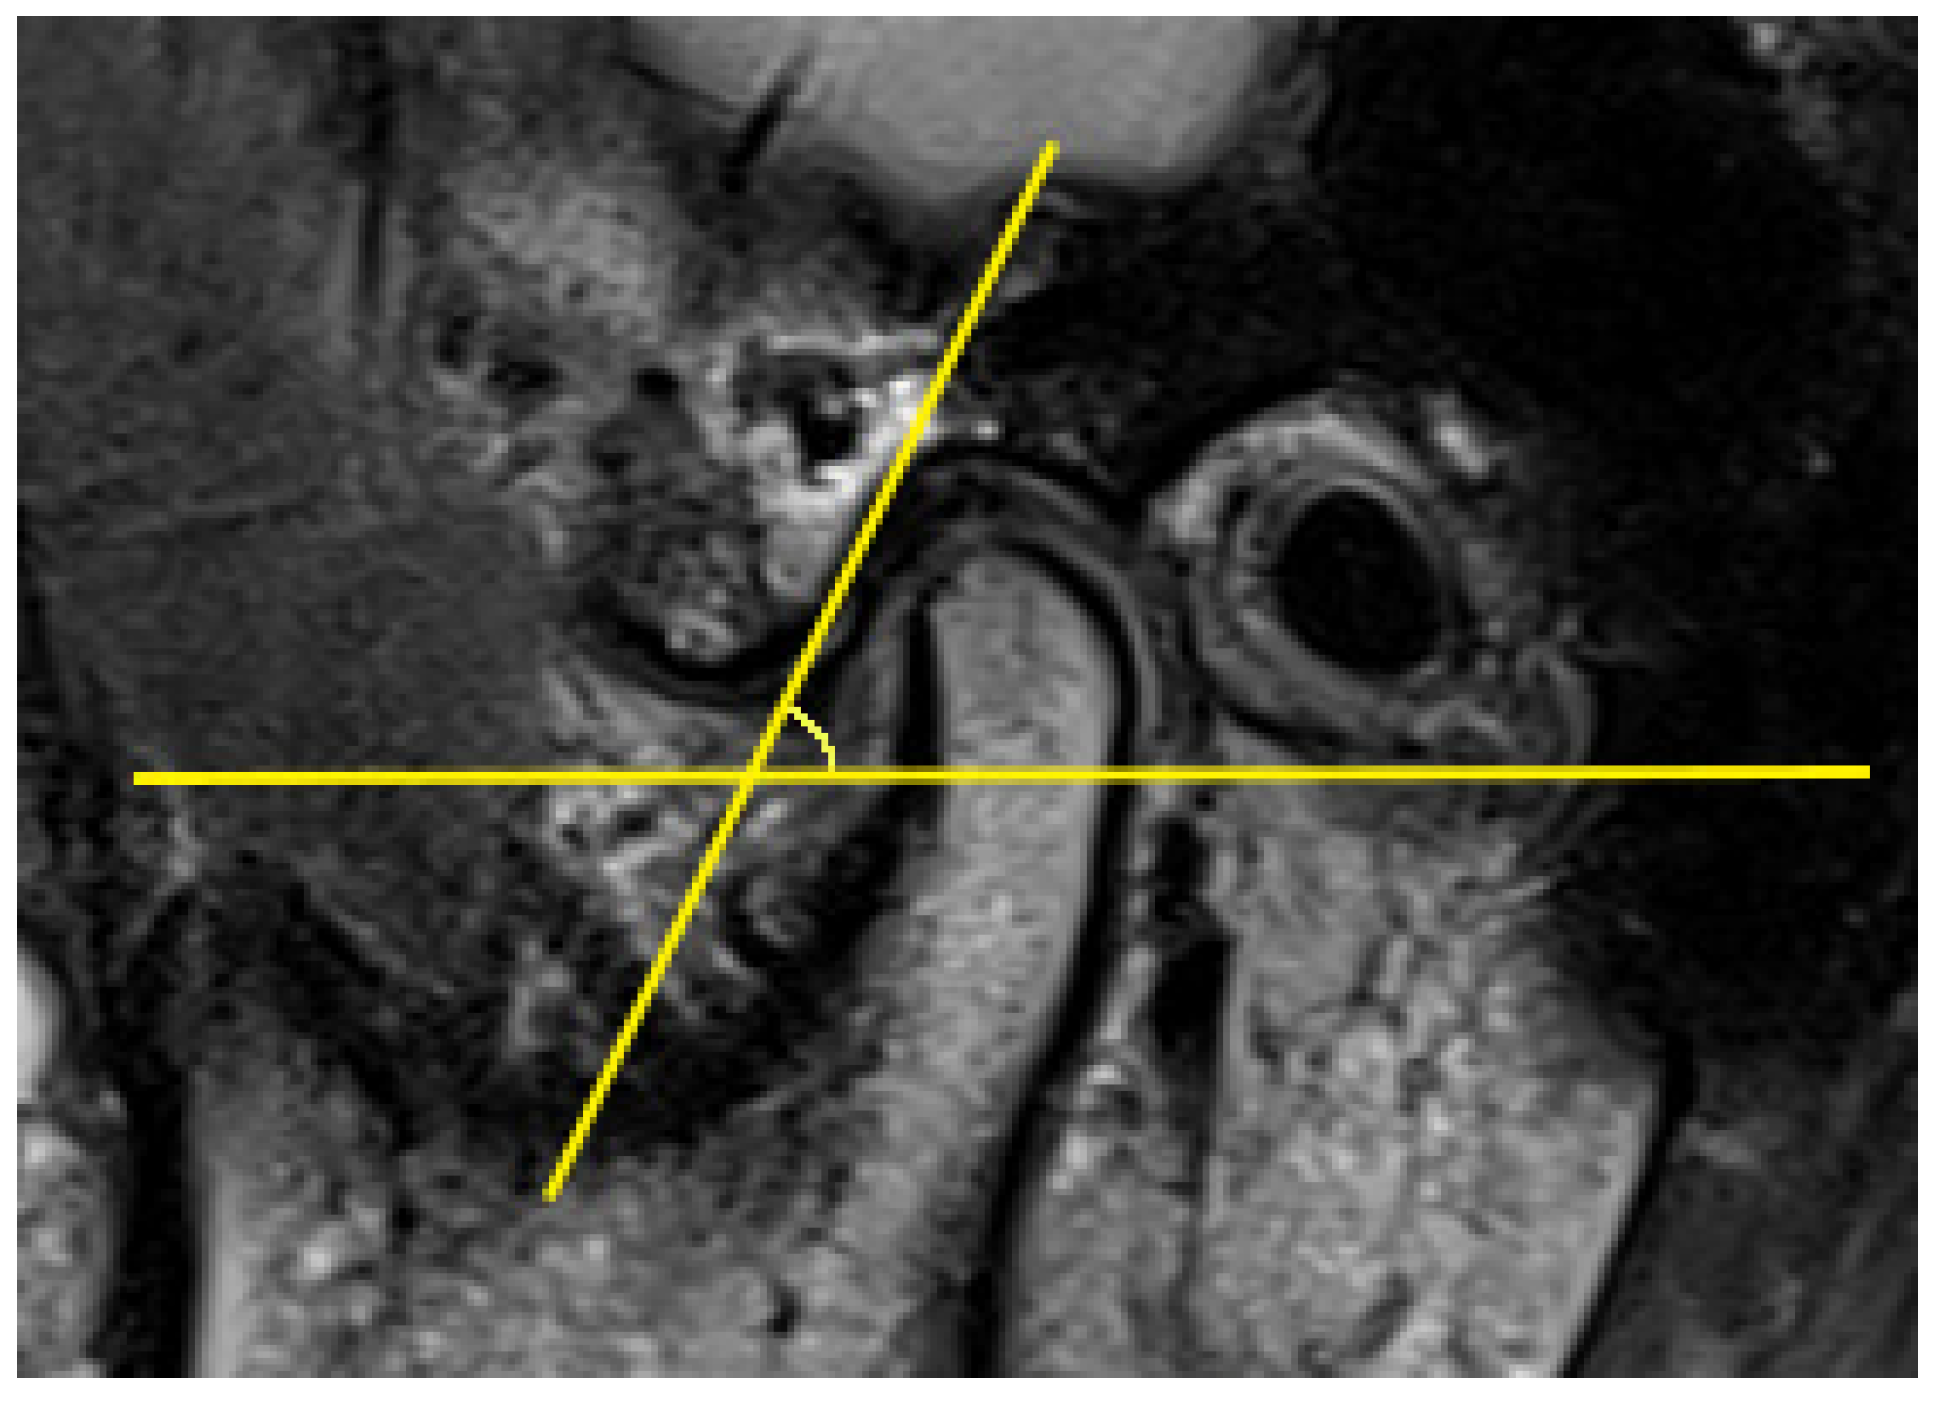

The AEI is defined as the angle formed by one of the lines that passes through the articular eminence and the horizontal reference plane [57]. In previous articles, two main methods have been described for evaluating the AEI, i.e., the “top-roof line” method and the “best-fit line” method, which are reliable and have already been used in studies. The “top-roof line” is obtained by connecting the crest point of the articular eminence and the roof of the mandibular fossa (Figure 2). The angle between the “top-roof line” and the horizontal reference plane is related to the height of articular eminence, which focuses on the localization of the tubercle in relation to the mandibular fossa and depicts the morphology of articular eminence better. The “best-fit line” method was defined as the angle between the tangent line drawn to the posterior slope of the articular eminence and the horizontal reference plane, which is directly related to the movement direction of the condyle-disk complex and reflects the actual condylar path (Figure 3) [26,30,31,41,57,58]. Five of 16 articles selected in this systematic review used the “top-roof line” method [14,17,18,43,49]; eight articles used the “best-fit line” method [19,20,40,41,42,45,46,48]; two articles used both the “top-roof line” method and the “top-roof line” method to evaluate the AEI [3,47], and the other article used the angle between tangent line from the uppermost point of the glenoid fossa and the true horizontal line as AEI [44]. Although the three mentioned methods all represent the inclination of the articulator eminence, the features they focus on are different. Therefore, they should be considered separately.

Figure 3.

Representative images of the “best-fit line” method, the articular eminence inclination (AEI) defined as the angle between the tangent line drawn to the posterior slope of the articular eminence and the horizontal reference plane.